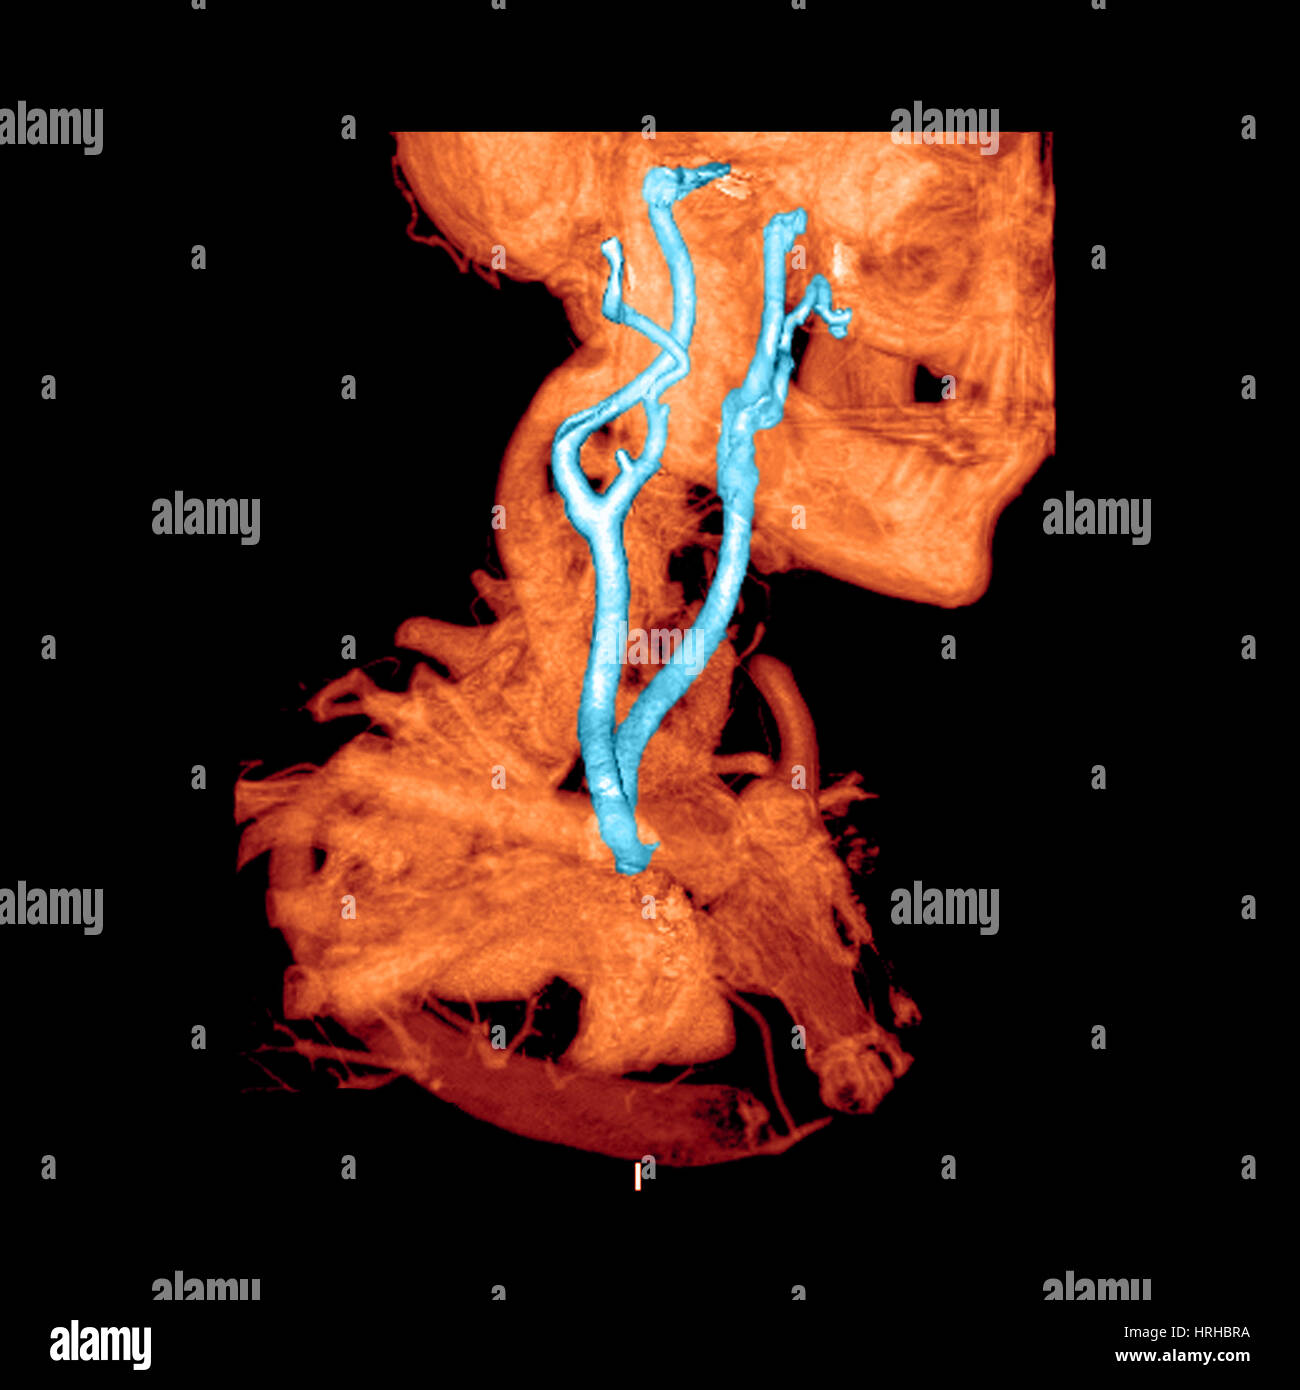

From www.alamy.com

3D CTA of Carotid Arteries Stock Photo Alamy Stethoscope Carotid Artery — narrowing of a carotid artery produces turbulent blood flow. in the head and neck, these auscultatory sounds may originate in the heart (cardiac valvular murmurs radiating to the neck), the cervical arteries (carotid. carotid artery disease may be suspected if a doctor hears a whooshing sound (called a bruit) while listening to a patient’s neck with. Stethoscope Carotid Artery.